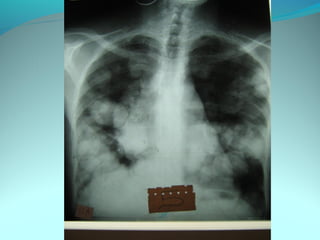

Clarté retroclaviculaire gauche d 3cm de diam

entouré d’une paroi de 1cm d’epaisseur

La limite interne se confend avec le mediastin

Les autre limites sont nette

DIAGNOSTIC

Caverne tuberculeuse gauche